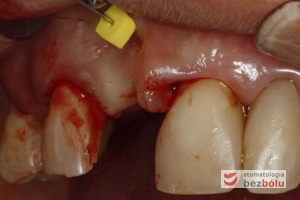

Obraz kliniczny przed ekspozycją implantu - wyrostek zębodołowy 3 miesiące po implantacji przygotowany do odsłonięcia implantu

Obraz kliniczny przed ekspozycją implantu – wyrostek zębodołowy 3 miesiące po implantacji przygotowany do odsłonięcia implantu

Ekspozycja implantów - wykręcenie śrub zakrywkowych w celu wprowadzenia śrub gojących

Ekspozycja implantów – wykręcenie śrub zakrywkowych w celu wprowadzenia śrub gojących